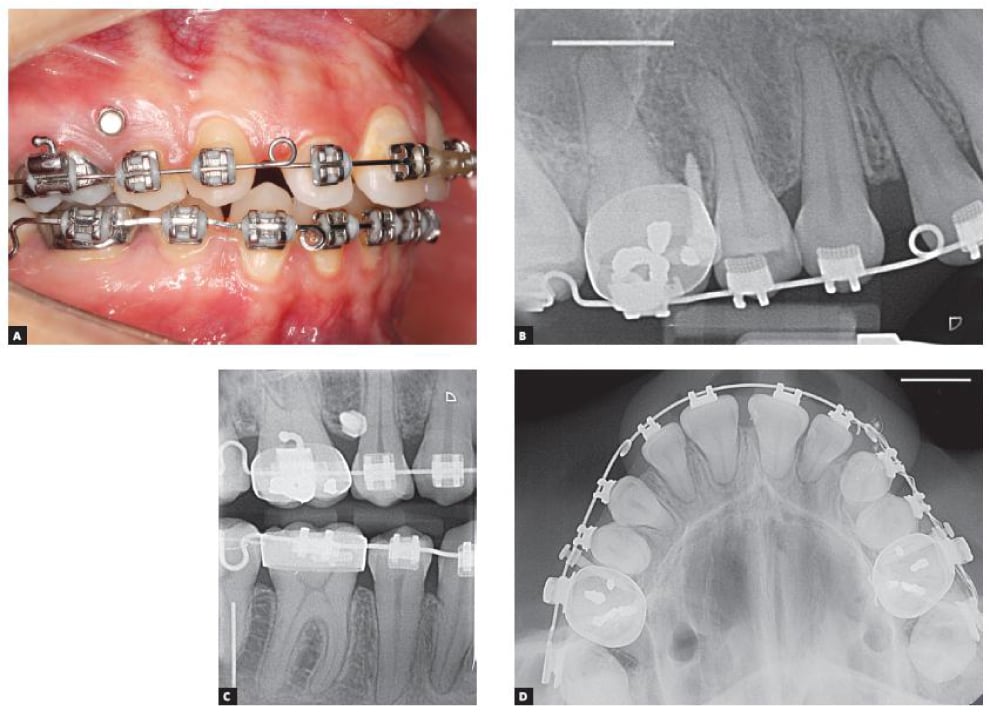

Temporary Anchorage Devices (TADs) have transformed orthodontic treatment by providing absolute anchorage without relying on patient compliance. While traditional methods like headgear or interarch elastics can be effective, TADs offer superior precision and efficiency in specific clinical scenarios. One of the most common applications is molar distalization, where TADs enable controlled, predictable movement without the need for bulky appliances or patient cooperation. Unlike headgear, which depends on consistent wear, TADs ensure continuous force application, making them ideal for non-compliant patients or cases requiring unilateral correction.

Another key scenario where TADs excel is intrusion of overerupted molars or anterior teeth. Traditional mechanics often struggle with intrusive movements due to reactive forces that can cause unwanted tooth displacement. With TADs, orthodontists can apply direct intrusive forces without reciprocal effects, achieving efficient and stable results. This is particularly valuable in open bite corrections or pre-restorative cases where precise tooth positioning is critical. Additionally, TADs simplify orthodontic camouflage treatment for skeletal discrepancies by allowing controlled tooth movement without surgical intervention, making them a game-changer for borderline surgical cases.